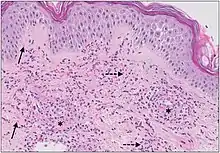

Micrograph of cutaneous small-vessel vasculitis. The section shows all features of leucocytoclastic vasculitis. A mixed inflammatory cell population surrounding the postcapillary venules of the superficial dermis. The infiltrate consists of neutrophils with nuclear dust (dashed arrows) and shows high affinity for the vessels. Features of vascular injury are shown including fibrinoid necrosis (asterisks) and erythrocyte extravasation (solid arrows).[11]